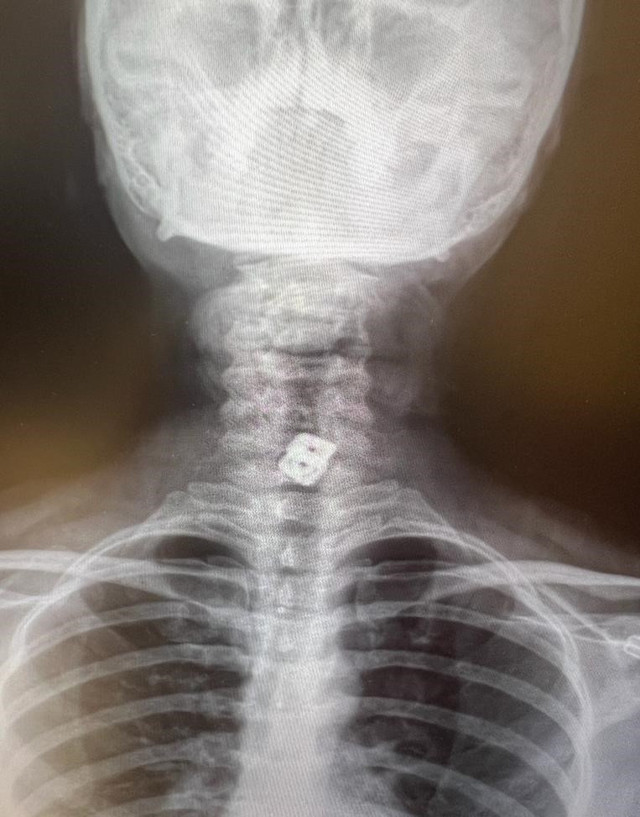

Metalik aparat gırtlağı delerek mideye inmiş

“O hastanede beyin ve sinir cerrahisi uzmanı tarafından ameliyata alınan Sultan Tıraş’ın boyun omuruna konulan iki aparattan biri çıkarılmış, ancak diğerinin yemek borusunu delip mideye indiği belirlenmiş. İlgili hekim bana ulaşarak bilgilendirmeyi yaptı ve hastayı hastanemize sevk etti. Yoğun bakıma alınan hastaya yaptığımız detaylı tetkikler ve klinik değerlendirme sonucu mediyastenit (ciddi göğüs enfeksiyonu) belirlendi. Bu ciddi bir sorun olup, hayati riski yüksektir. En hızlı şekilde tıbbi tedaviye başladık, gastroenteroloji bölümümüzde endoskopi yapıldı. Yemek borusunda oluşan delik ve delikten mideye inen metalik cerrahi aparat görüldü. Göğüs kafesi içinde ciddi bir iltihap ve hava birikimi vardı. Hasta yakınları durum ile ilgili bilgilendirildi, riskler kendileri ile paylaşılarak hastamıza tıbbi müdahale edebilmemiz gerekli onayları alındı.”

Hastanın endoskopik incelemesinde yabancı cisim tespit edildi

“Endoskopi sırasında hastanın midesinde metalik bir oluşuma benzer yabancı cisim ile yemek borusunda ülser görünümü izledik. Lezyon bölgesi belirlendikten sonra hastamızın tedavisi için Göğüs Cerrahisi Bölümümüze durumu ilettik. Prof. Dr. Levent Elbeyli Hocamız hastamızın sağlığına kavuşması için gerekli tedaviyi planlayarak, başarılı bir operasyonla sonuca ulaştı. Emeği geçen herkese teşekkür ediyorum. Hastamızı sağlıklı bir ömür diliyorum.”